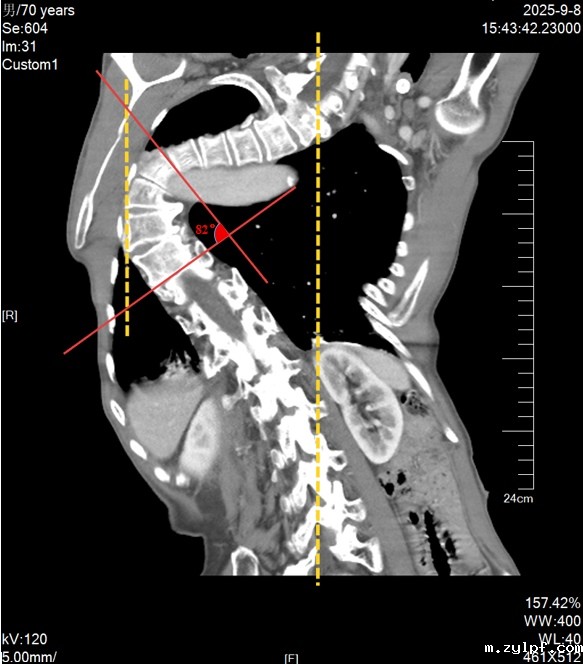

脊柱侧弯胸廓畸形

患者70岁高龄,因右肺结节需要行手术治疗。但其患有极重度脊柱侧弯,胸廓严重畸形,侧弯最大处抵及右侧胸壁,术前CT提示双侧肺炎,动脉血气分析结果显示已达呼吸衰竭临界值,麻醉管理面临三大难题:气道变异,脊柱侧弯致气管、支气管解剖结构严重扭曲,传统单肺通气工具放置及定位困难,易导致肺隔离失败或气道损伤;氧合耐受差,患者本身肺功能不全,对单肺通气期间的氧合耐受能力极低,如何维持有效的通气和氧合是麻醉管理的核心难题;操作空间受限,畸形脊柱横卧右侧胸腔将其一分为二,使得手术操作空间更为狭小,这对单肺通气提出更高要求,即手术侧肺叶必须充分塌陷,才能为外科医生提供满意的肺隔离条件,同时需最大限度减少气道损伤以利术后快速康复。